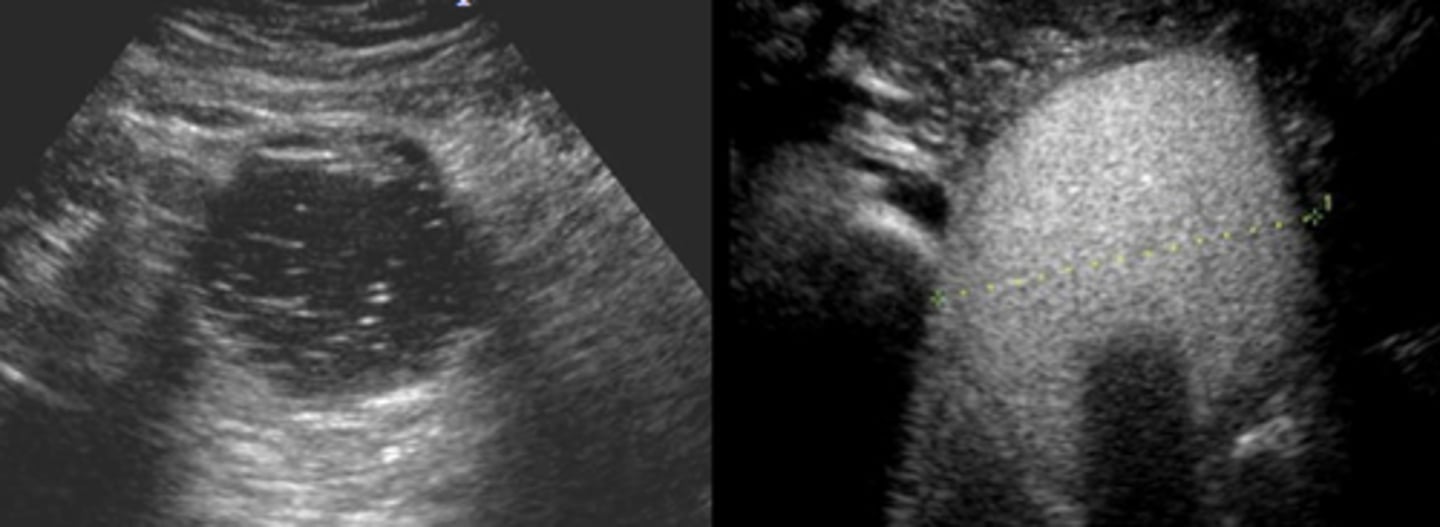

-ultrasound provide more anatomic detail than physical exam

-need FNA to check malignancy

imaging used to assess thyroid noddules

mostly solid, hyperechoic nodules

US findings of malignant thyroid nodules

-US shows solitary nodule

-most are euthhyroid

-RAIU shows a cold nodule (hot if bigger)

solid and hypoechoic

malignant nodules on sonography appear